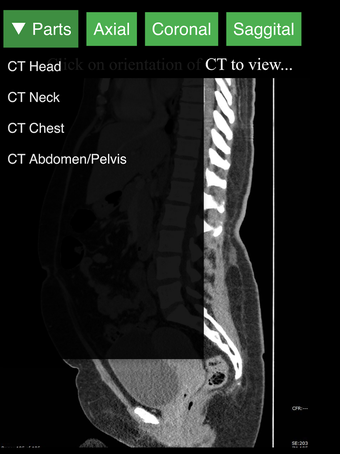

Radiology CT Viewer - полезный инструмент для врачей, медицинских студентов, радиологических техников и других медицинских специалистов, которые хотят узнать больше о человеческом теле и его анатомии. Приложение содержит подробные сечения наиболее важных частей тела. Кроме того, оно содержит интерактивную 3D-модель, которая позволяет вращать, увеличивать и перемещать камеру вокруг изображения, чтобы получить лучший обзор анатомии.

Если вы ищете инструмент, который поможет вам узнать больше о человеческом теле, Radiology CT Viewer - отличный выбор. Он содержит подробные иллюстрации и интерактивную 3D-модель.